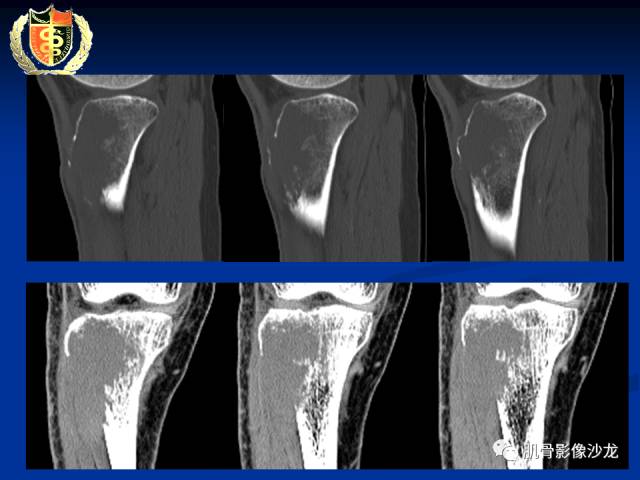

骨淋巴瘤及软骨肉瘤两例CT及MR影像表现

胫骨近端骨质破坏,边缘不清,破坏边模糊,骨皮质不完整,可见软组织肿块突破骨皮质外,病灶累及关节面下,无关节内累及,MRI病灶呈T2WI高信号,信号均匀,考虑:恶性肿瘤性病变,淋巴瘤先考虑,转移瘤及其他待排

内部密度和信号比较均匀,无钙化,无骨膜反应,骨质破坏边缘不清晰,软组织较明显,弥散受限,首先不能排除淋巴瘤